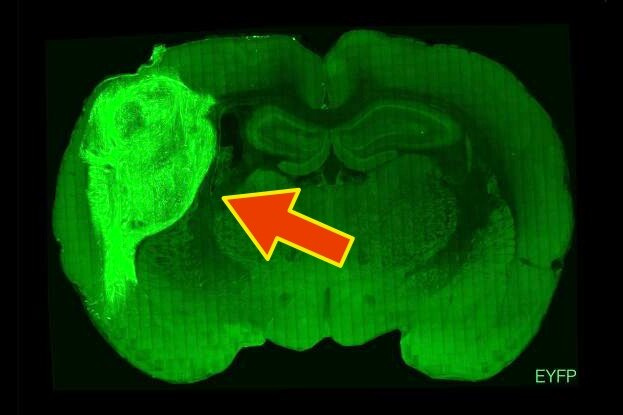

Трехмерные органоиды, созданные из стволовых клеток и напоминающие упрощенную модель коры головного мозга человека, соединены и интегрированы с окружающей тканью в коре каждой крысы, образуя функциональную часть собственного мозга грызуна, проявляющую активность, связанную с сенсорным восприятием.